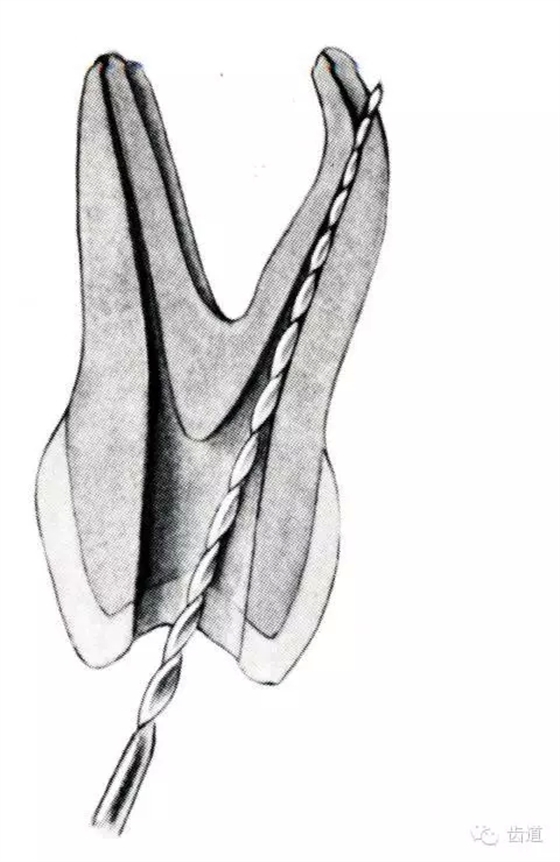

根管壁穿孔多在根管彎曲處。

根管機(jī)械預(yù)備時(shí),使用根管器械未按由小到大的順序使用。

器械進(jìn)入根管方向與根管走行方向不一致。

根管內(nèi)遇阻力強(qiáng)行進(jìn)入。